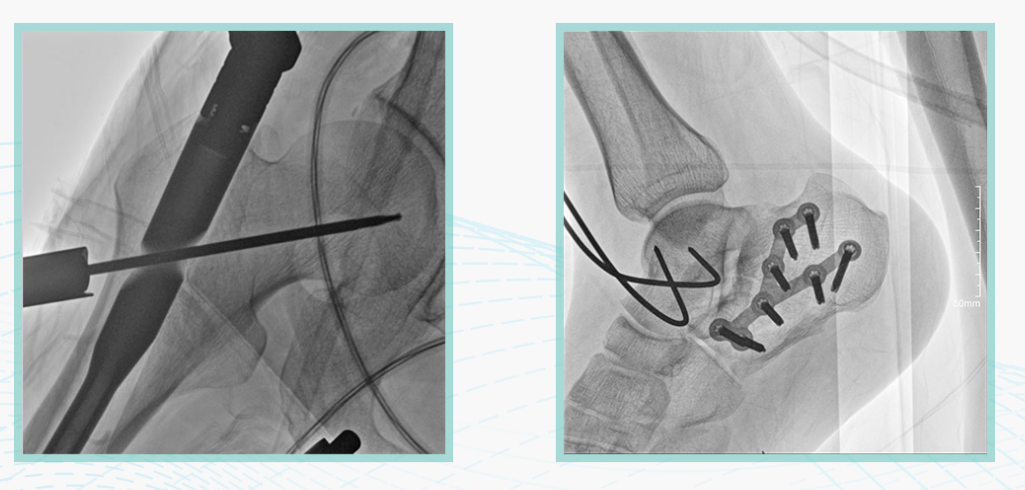

388vip太阳集团科技悦画移动C臂X线摄影系统,采用了业内技术最尖端的CMOS探测器。基于性能优异的针状CSI闪烁体涂层和高灵敏度的CMOS感光芯片,悦画可以实现在超低X线剂量条件下实现高清晰影像成像,相较于一般的影增移动C臂和平板C臂,动态范围更高,影像的层次感和对比度更好。

在产品的性能参数设计上,悦画的像素可达到200万,空间分辨率可达到3.2线对,采用16bit的影像灰度,悦画在影像后处理上,通过SPI金字塔图像算法,支持摄影、脉冲透视影像、连续透视等多种模式下的影像采集,动态透视影像视频支持保存与回放。双大屏的设计,透视影像支持三档放大,保证临床影像读取的便利。

悦画在影像的伪影处理上,也积累多项图像处理专利技术。通过对植入物的精准识别,悦画能够精准祛除植入物伪影与运动伪影,保证高质量的影像输出,无论是影像的对比度、分辨率(清晰度)相较于市面上的移动C臂产品都更胜一筹。